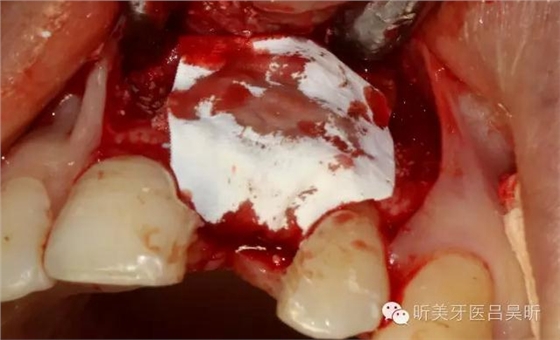

骨缺損區(qū)植如BIO-OSS 骨粉

植骨完成后覆蓋鈦網(wǎng)

使用1.4mm直徑固位釘固定鈦網(wǎng),確保骨粉充填密實(shí),鈦網(wǎng)無邊緣翹起。

修剪BIO-GIDE膠原膜

在鈦網(wǎng)上覆蓋第一層膠原膜

在穿通區(qū)腭側(cè)覆蓋第二層膠原膜

唇側(cè)雙側(cè)蓋膜